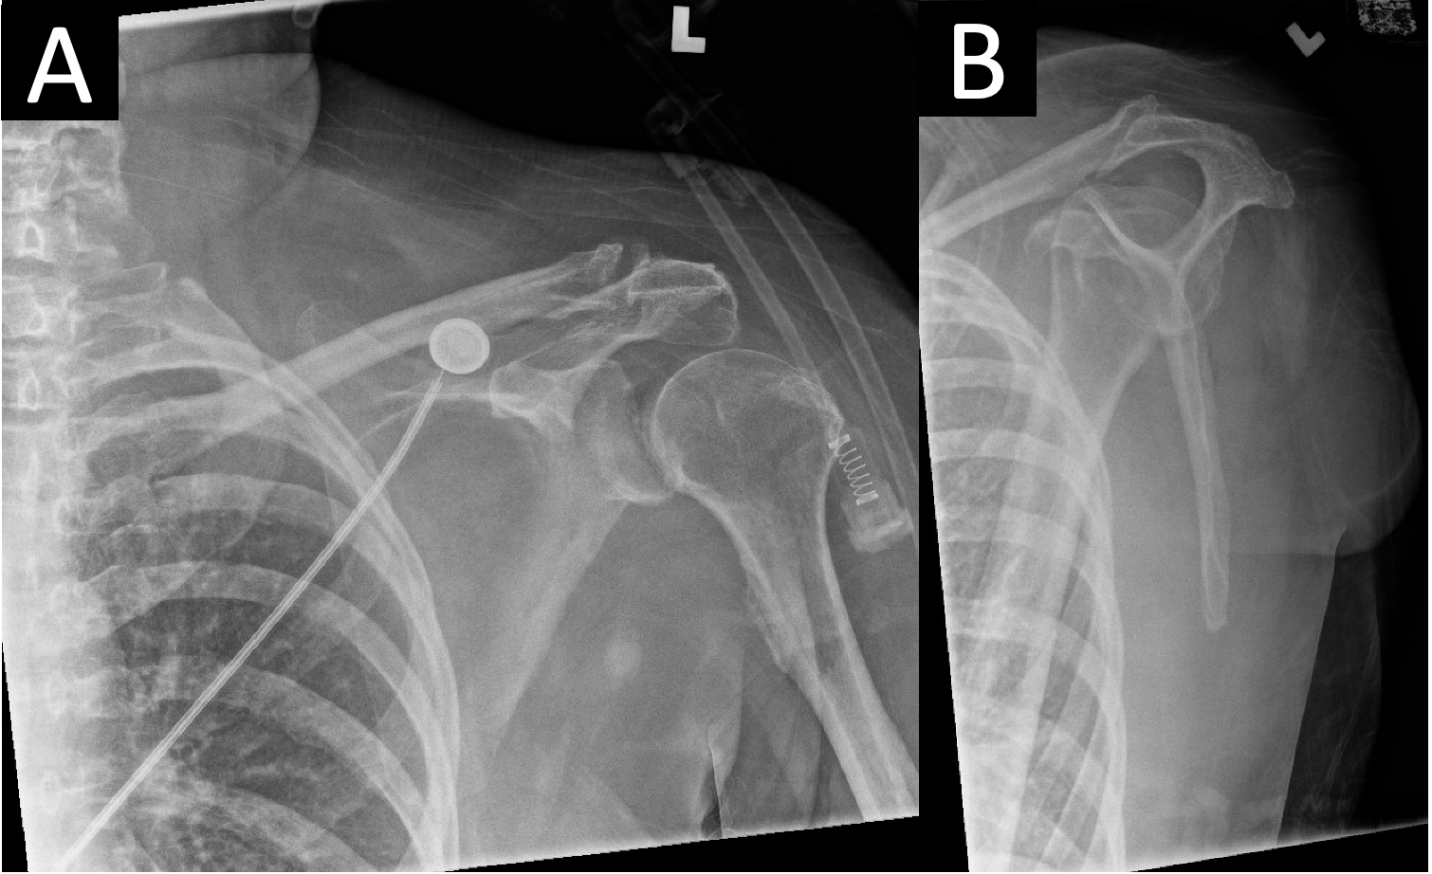

Clinical examination of the left upper extremity was notably benign (Fig. 2) without erythema, bullae, induration, crepitus, or notable wounds. Due to her mental status, sensorimotor examination could not be obtained, but distal pulses were palpable, and passive movement of the extremity did not appear to elicit pain or alter vital signs. Radiographs of the left shoulder revealed pneumarthrosis (Fig. 3a and b).

Figure 3: (a and b) Anteroposterior(a) and lateral scapula (b)radiographs of the left shoulder revealed a concentric glenohumeral joint with no osseous abnormality or radiopaque foreign body. A small crescent of radiolucency consistent with pneumarthrosis medial to the humeral head is visible in the glenohumeral joint.